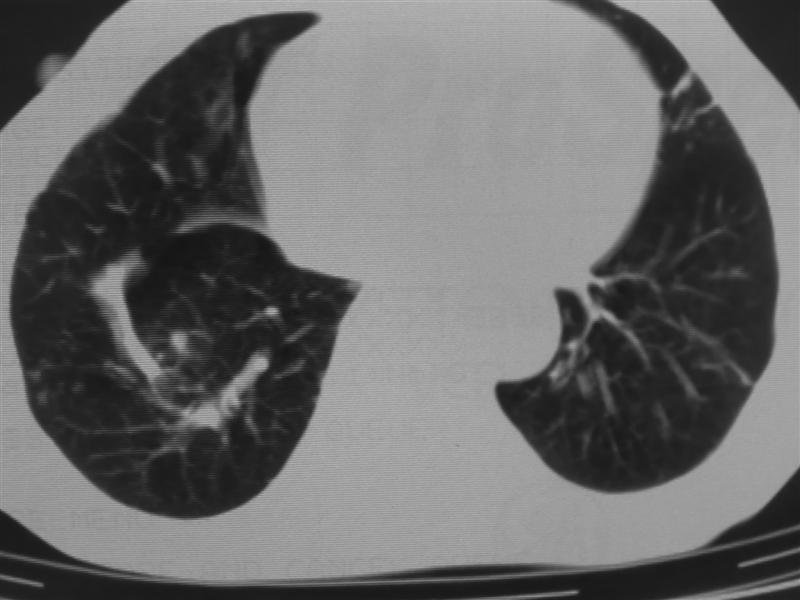

支持右下肺癌伴肺内转移

右下肺周围型肺癌伴双肺右侧叶间 胸膜及右肺门淋巴结转移

肺癌伴肺、胸膜转移